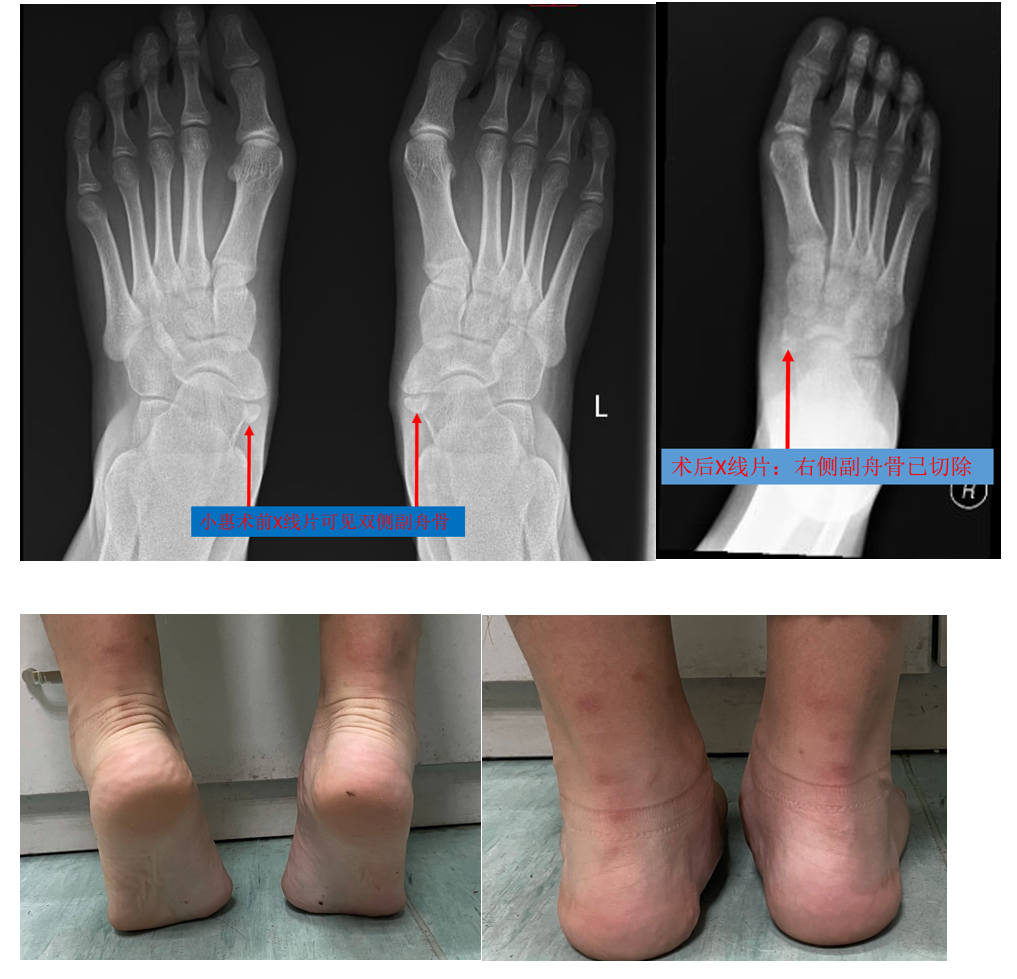

手术治疗是将副舟骨切除,并切除多余突出的舟骨结节,使之与距骨和楔骨

一例 小儿副舟骨,大家看看,如何诊治?